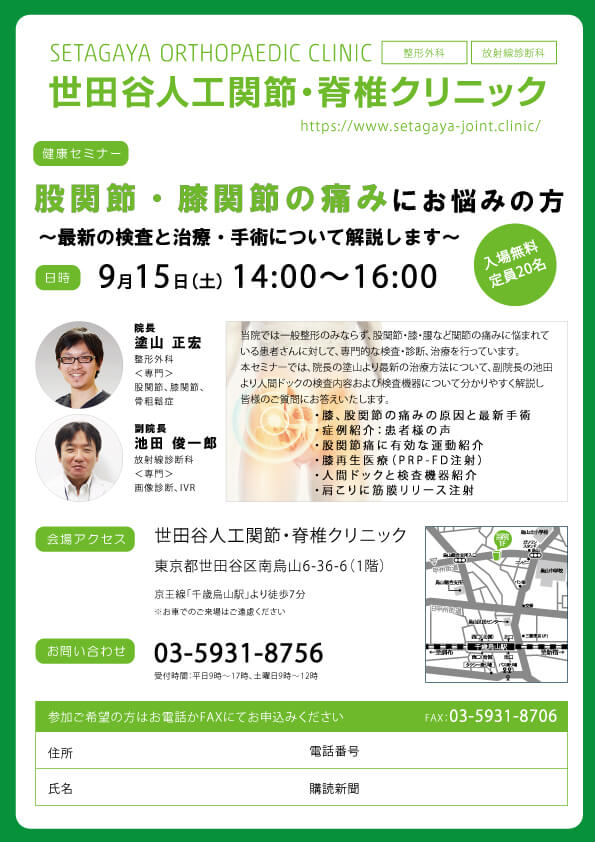

第5回院内講座開催報告です。

今回は2019年2月9日(土)14時~16時で開催しました。

前回が2018年9月の開催でしたので

約5か月ぶりの開催となりました。

今後も定期的に院内講座を開催する予定ですので、

今回ご都合が悪く参加できなかった方は

また次回参加していただけたらと思います。